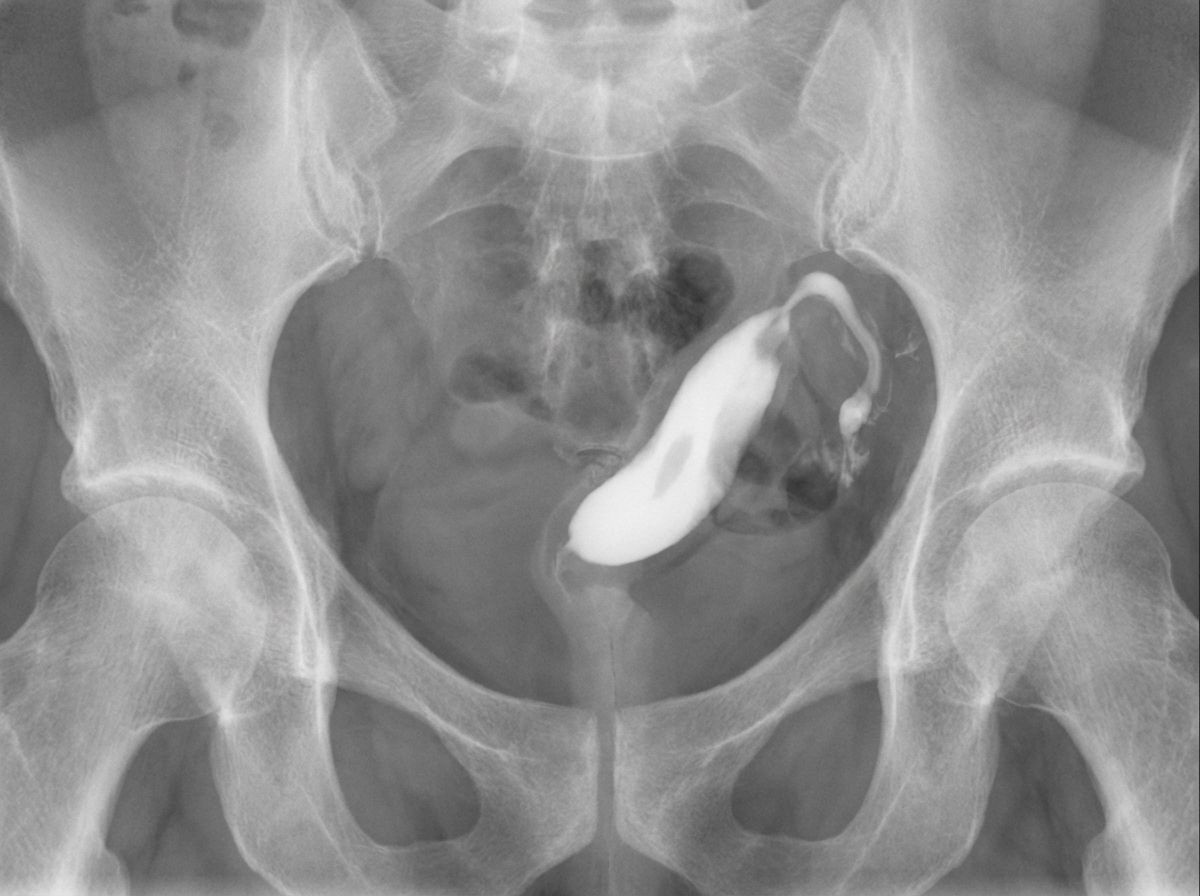

A female patient presents with complaints of infertility. Hysterosalpingography (HSG) findings are described as follows. What is the most likely diagnosis?

Explanation: ***Unicornuate uterus*** - HSG shows a characteristic **single banana-shaped uterine cavity** with only **one fallopian tube** visible, representing incomplete development of one Müllerian duct. - Associated with **increased infertility** and **pregnancy complications** due to reduced uterine volume and potential **renal anomalies** on the same side. *Septate uterus* - HSG demonstrates a **normal external uterine contour** with an **internal septum** dividing the cavity, creating two compartments. - The **intercornual angle is acute (<90°)** and both fallopian tubes are present, unlike the single tube in unicornuate uterus. *Bicornuate uterus* - HSG reveals **two separate uterine horns** with an **obtuse intercornual angle (>90°)** and a **fundal indentation** visible externally. - Both **fallopian tubes are present** and the external contour shows a **heart-shaped** appearance, contrasting with the single cavity in unicornuate uterus. *Uterus didelphys* - HSG shows **complete duplication** with **two separate uterine cavities** and **two cervices**, requiring separate contrast injections. - Represents **complete non-fusion** of Müllerian ducts, unlike the partial development seen in unicornuate uterus.

Explanation: **Explanation:** The clinical presentation and hysterosalpingography (HSG) findings are classic for **Genital Tuberculosis**, caused by *Mycobacterium tuberculosis*. **Why the Correct Answer is Right:** Genital TB is a significant cause of tubal factor infertility in developing countries. It typically spreads hematogenously to the fallopian tubes (affected in 90-100% of cases). The characteristic HSG findings include: * **Beaded appearance:** Caused by multiple strictures and scarring along the tube. * **Clubbing of the ampulla:** Resulting from fimbriated end occlusion and distal dilatation. * **Lead pipe appearance:** Rigid, straight tubes due to chronic inflammation. * **Tobacco pouch appearance:** Eversion of the fimbriae. **Why Incorrect Options are Wrong:** * **Gonococcus & Chlamydia:** These are the most common causes of Pelvic Inflammatory Disease (PID). While they cause tubal blockage and hydrosalpinx, they typically present with acute symptoms and lead to "fimbriated end block" or "beaded" appearance less frequently than TB. Chlamydia is more associated with "silent" salpingitis and perihepitic adhesions (Fitz-Hugh-Curtis syndrome). * **Mycoplasma:** While it can cause cervicitis or PID, it is a rare cause of the specific chronic architectural distortions (beading and clubbing) seen in this scenario. **High-Yield Clinical Pearls for NEET-PG:** * **Gold Standard Diagnosis:** Endometrial biopsy for histopathology (showing giant cells/granulomas) and TB-PCR/Culture, ideally performed in the pre-menstrual phase. * **Most common site:** Fallopian tubes (100%) > Endometrium (50%) > Ovaries (20%). * **Schier’s Sign:** Calcified lymph nodes or pelvic calcifications on X-ray, highly suggestive of TB. * **Prognosis:** While antitubercular therapy (ATT) can treat the infection, the structural damage to the tubes is often irreversible, making IVF the preferred fertility treatment.